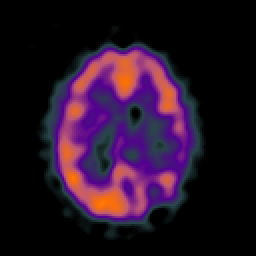

SPECT TC Study #5 -- Slice #34

[Home][Help][Clinical][Tour 1][Tour 2][Tour 3] Slice 34